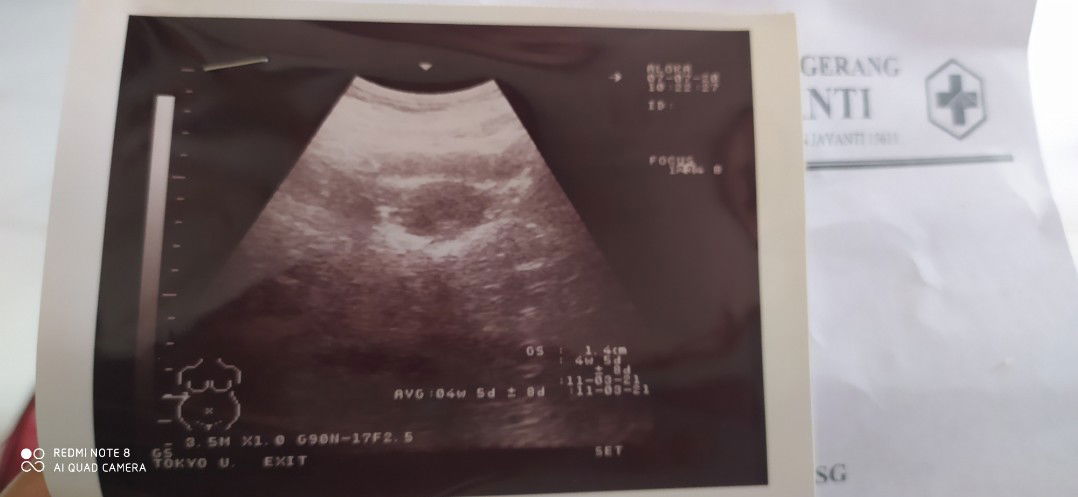

Menantikan saat menjadi ibu

keguguran

Umur kehamilan 4 Minggu 5 hari padahal sudah di nanti" selama 8 bulan pernikahan. Tapi Allah berkehendak lain...